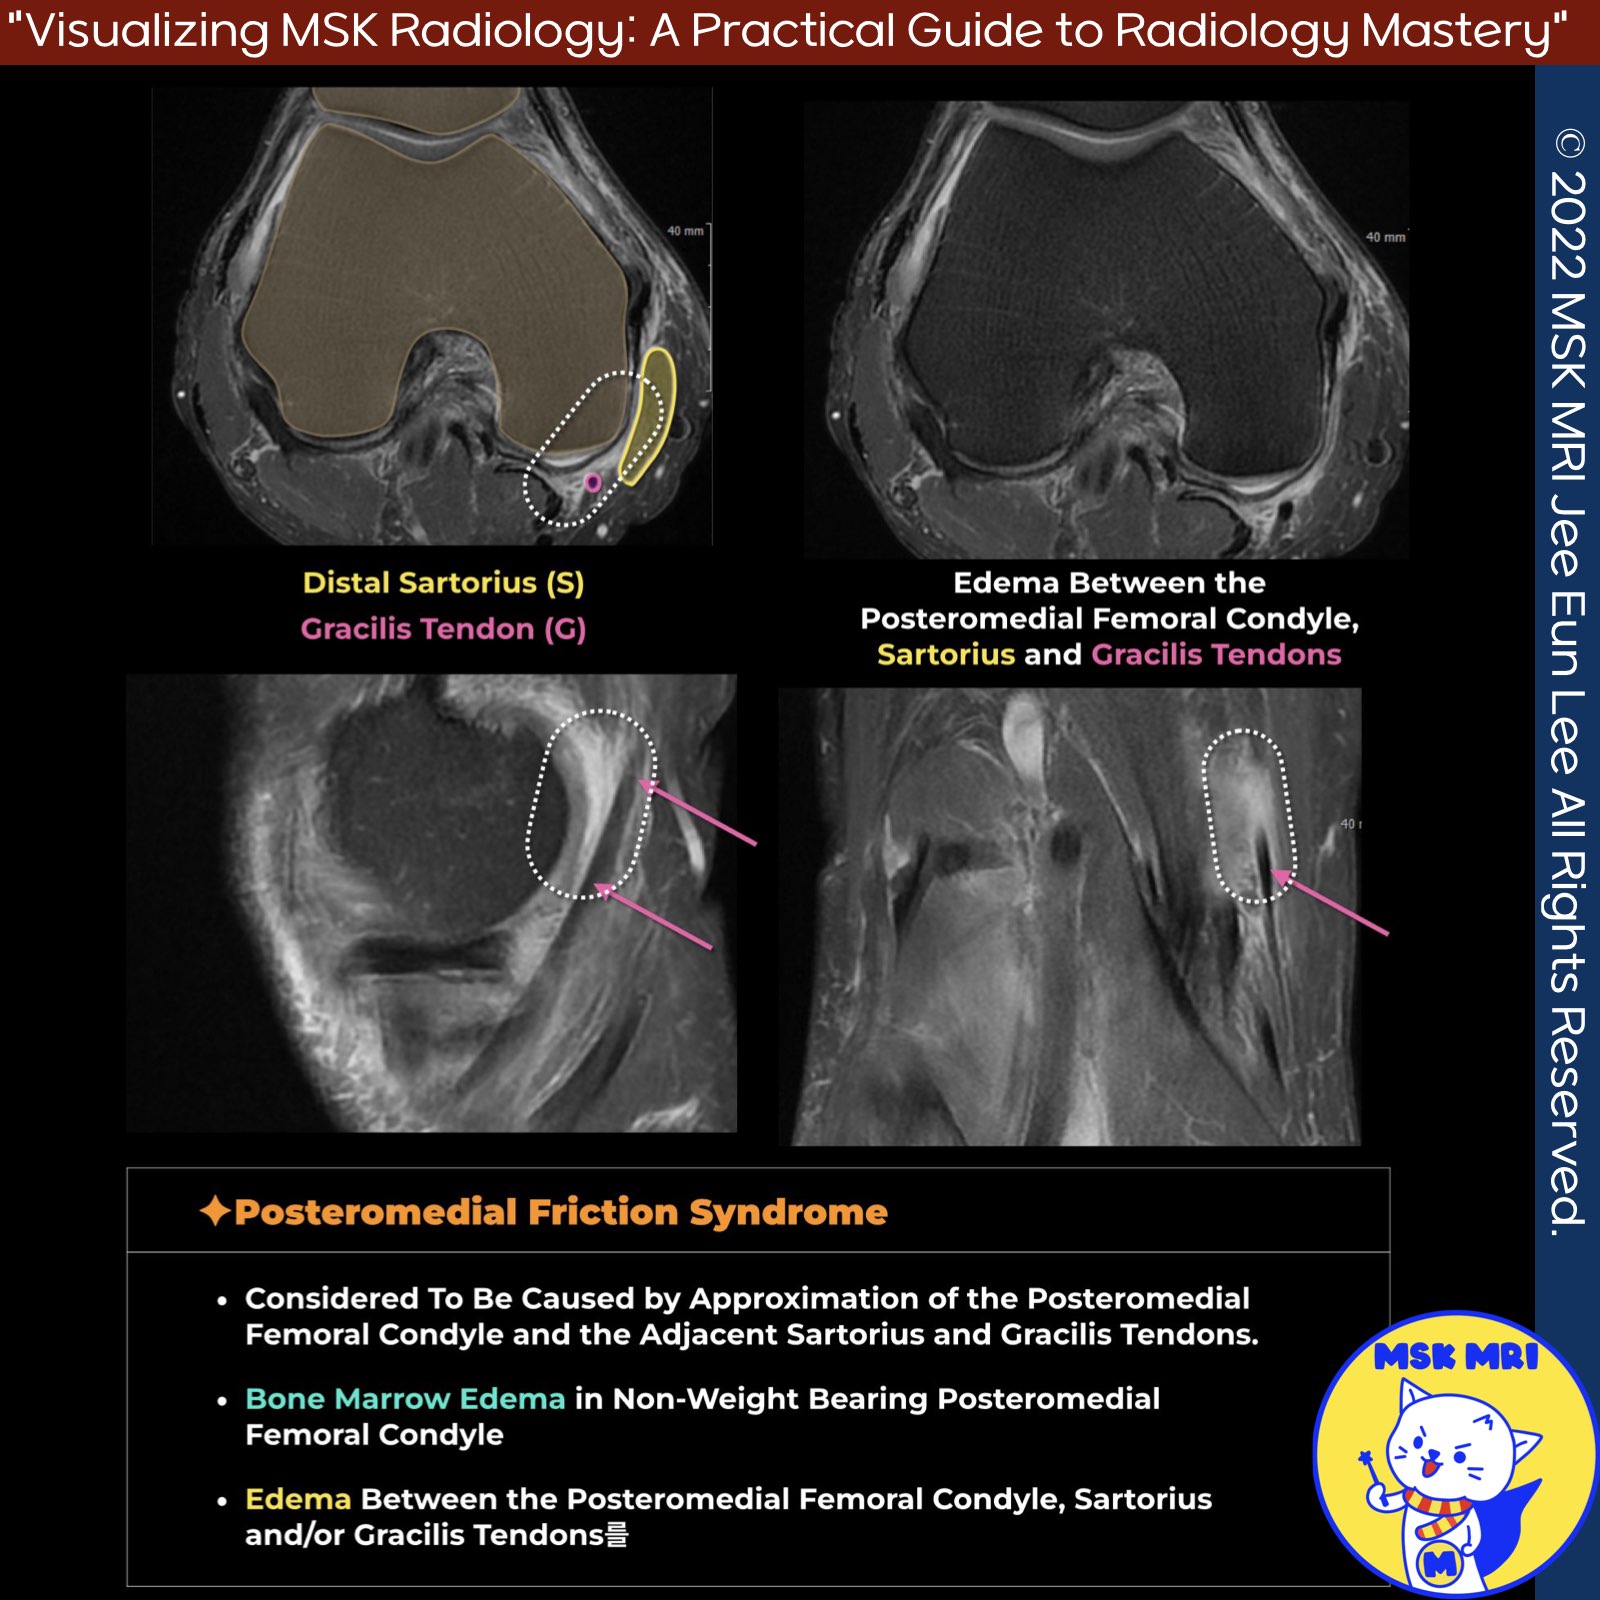

📌Posteromedial Knee Friction Syndrome

- Edema between posteromedial femoral condyle, sartorius and gracilis tendons

- Caused by approximation of posteromedial femoral condyle and adjacent tendons

- Occasional bone marrow edema in non-weight bearing posteromedial femoral condyle